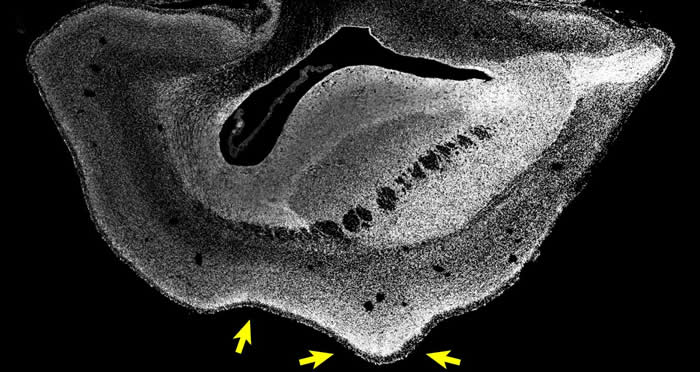

101日龄普通狨猴胎儿的大脑切片(Credit : Heide et al. / MPI-CBG)

(报道)ARHGAP11B是一种人类特有的基因,过去的研究认为它可能与大脑发育有关。近日,在《科学》发表的一项研究中,研究人员将ARHGAP11B基因转入普通狨猴胚胎内。结果显示,101日龄(正常出生时间前50天)的普通狨猴胎儿大脑的新皮质变大,且大脑表面折叠增加,其皮质板也发育得更厚。此外,研究还发现,一些在灵长类演化过程中数量增加的神经元类型,在这种转基因胎儿的大脑内也有所增加。这一研究证明,人类特有的基因ARHGAP11B的充分表达,会导致灵长类大脑变大,从而说明这一基因在人类大脑的演化过程中,起到了重要的作用。